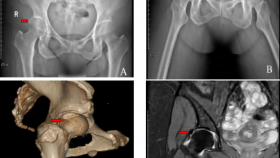

近日,我院小儿骨科联合运动医学科为一位12岁的胫骨平台骨折女童完成关节镜下手术。患儿入院后,小儿骨科医生为其完善了检查,发现患儿为左膝胫骨平台骨折,CT显示其胫骨平台塌陷0.5cm。儿童胫骨平台骨折比较罕见,治疗起来也比较棘手。因患儿年幼,骨骼发育尚未成熟,胫骨近端骨骺骺板未闭合,不适当的治疗可能会加重骨骺的损伤,影响患儿膝关节发育,同时,骨折累及胫骨关节面,打开膝关节直视下复位,又会造成关节内较大的损伤和皮肤瘢痕。经全科讨论,决定联合运动医学科发挥关节镜的优势,在关节镜下进行骨折闭合复位内固定微创手术治疗。经过充分术前准备,运动医学科主任葛兴涛和小儿骨科主任许洪涛联合实施了手术。术中,葛兴涛对患儿进行了关节镜检查,排除了关节内的其他损伤,直视下观察到关节面塌陷的情